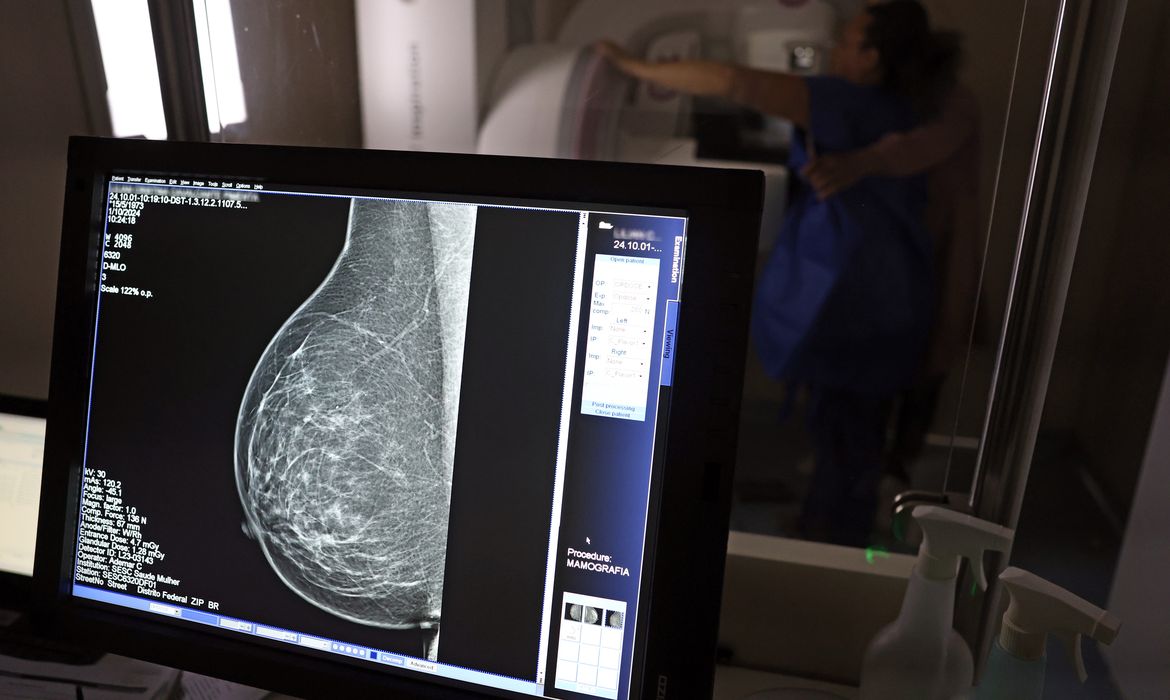

O direito já estava incluído na CLT desde 2018. A partir de agora, as empresas passam a ser obrigadas a divulgar essa informação, além de outras relacionadas a campanhas oficiais de vacinação contra o HPV e sobre o acesso a serviços de diagnósticos de cânceres de mama, próstata e de colo do útero.

O texto estende o uso das folgas também para a realização de exames preventivos do HPV, além dos de câncer que já estavam previstos na legislação anterior. A Lei 15.377 foi sancionada pelo presidente Luiz Inácio Lula da Silva e publicada na edição do Diário Oficial da União (DOU).